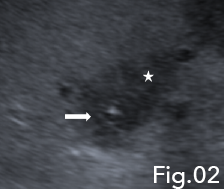

When there was minimal drainage from the catheter, a repeat ultrasound was undertaken to assess resolution. B-mode ultrasound demonstrated a solid low reflective area, presumed to be an abscess with a drainage catheter correctly positioned (Fig 2). The abscess had reduced in size in comparison with the previous examination, however, a new hypoechoic region was noted superiorly to the first abscess (Fig 3) giving rise to suspicion of new abscess formation. IV and IC CEUS were undertaken following local protocols. IV CEUS utilised 2.4 ml of SonoVue (Bracco, Milan) administered through a cannula situated in the left antecubital fossa, followed by a 10ml bolus of saline solution. IC CEUS utilised 0.1 ml of SonoVue (Bracco, Milan) diluted in 50 ml of saline administered via the hepatic drainage catheter.

Fi 2: Note the hypoechoic but more solid appearance of the abscess (star) with the catheter tip seen within (arrow).